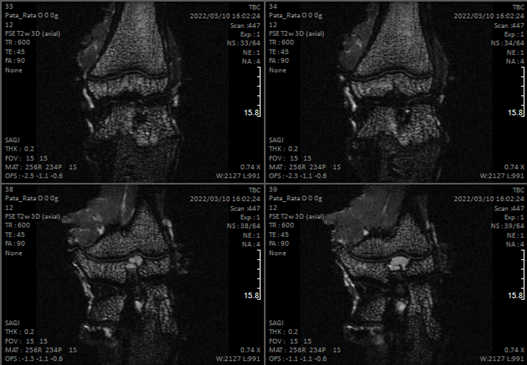

- Bone-level imaging, distinguish between bone material from soft tissue.